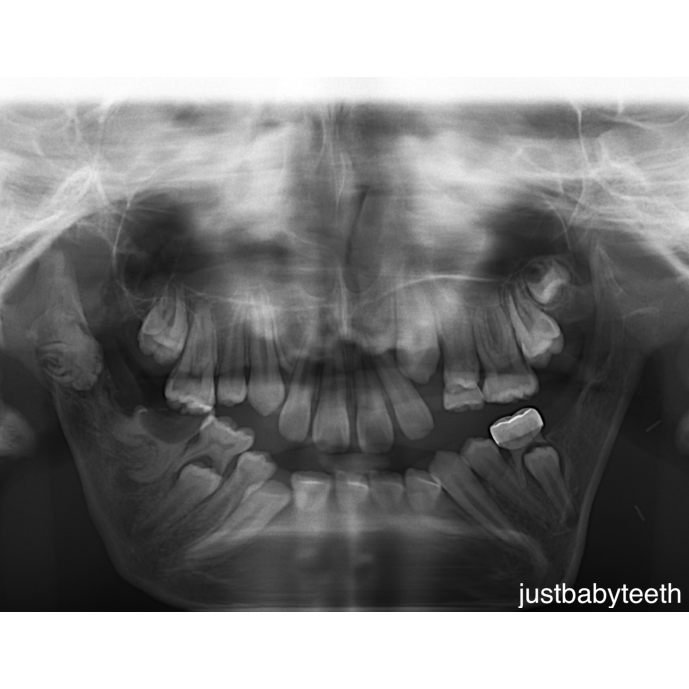

Dx: missing #18 and #19, malformed/carious #30, malformed #31

MDO is not without its complications. Because this procedure takes place at the site of the developing tooth buds of the mandibular molars, it is only logical that they can be adversely affected. In our panoramic radiograph, you can see #18 and #19 are completely missing and #30 and #31 are malformed. After consultation with OMFS and plastics, it is recommended that we monitor due to the difficult nature of this case (thin mandible and limited opening). Future treatment needs may include extraction and implant placement.

Let’s look into the literature. In one study, 17 patients with a history of MDO were evaluated. Of the 17 patients and 63 mandibular molars, 13 patients and 18 mandibular molars were affected with changes ranging from “root malformations, hindered tooth development and the destruction of tooth follicles.”